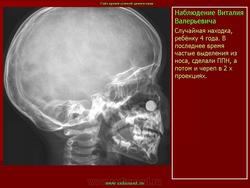

Пломбировочный материал, хронический гайморит

Приложения: